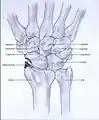

Post-traumatic osteoarthritis can be classified into four stages.[1][6] These stages are similar between SLAC and SNAC wrists. Each stage has a different treatment.

- Stage I: the osteoarthritis is only localized in the distal scaphoid and radial styloid.

Stage I